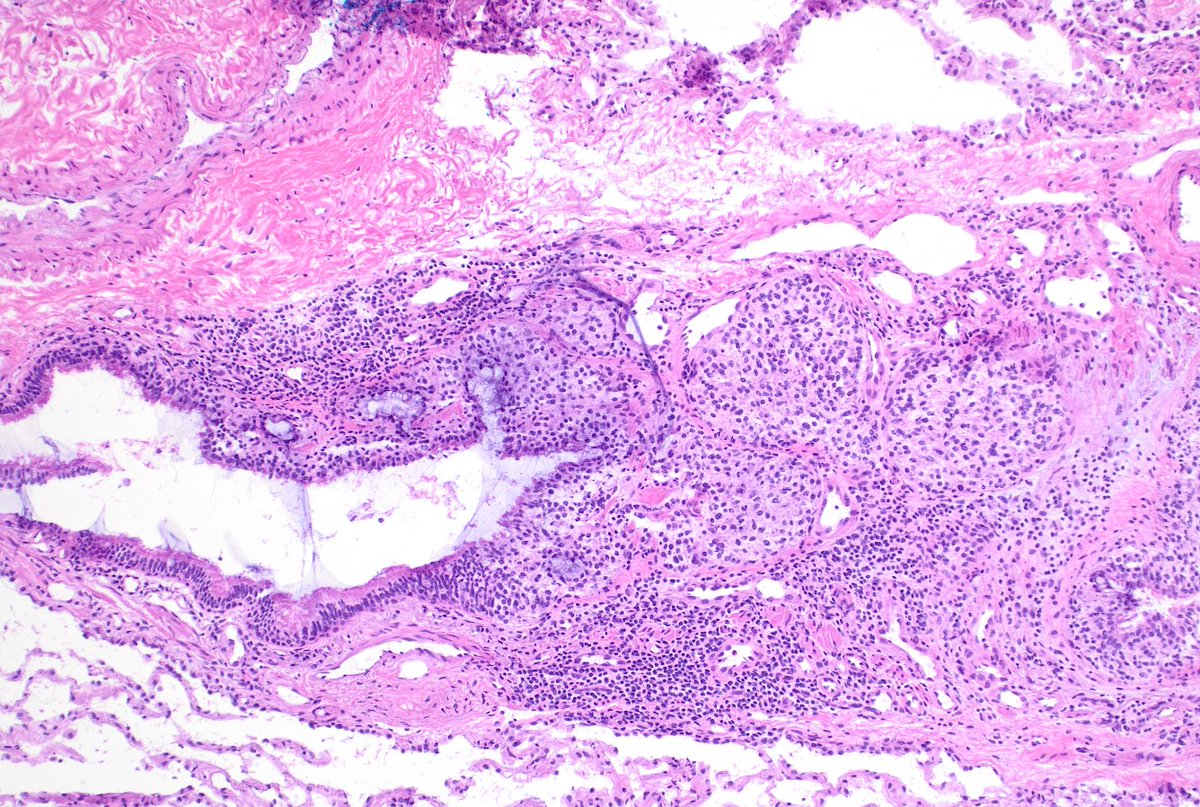

Diagnosing granulomatosis with polyangiitis on small biopsies (especially if not considering it) is very challenging. ANCA serologies, negative cultures, and pathologic suspicion were crucial in this case. Not everything is cancer at a cancer center. #lungpath #pathology #moffitt